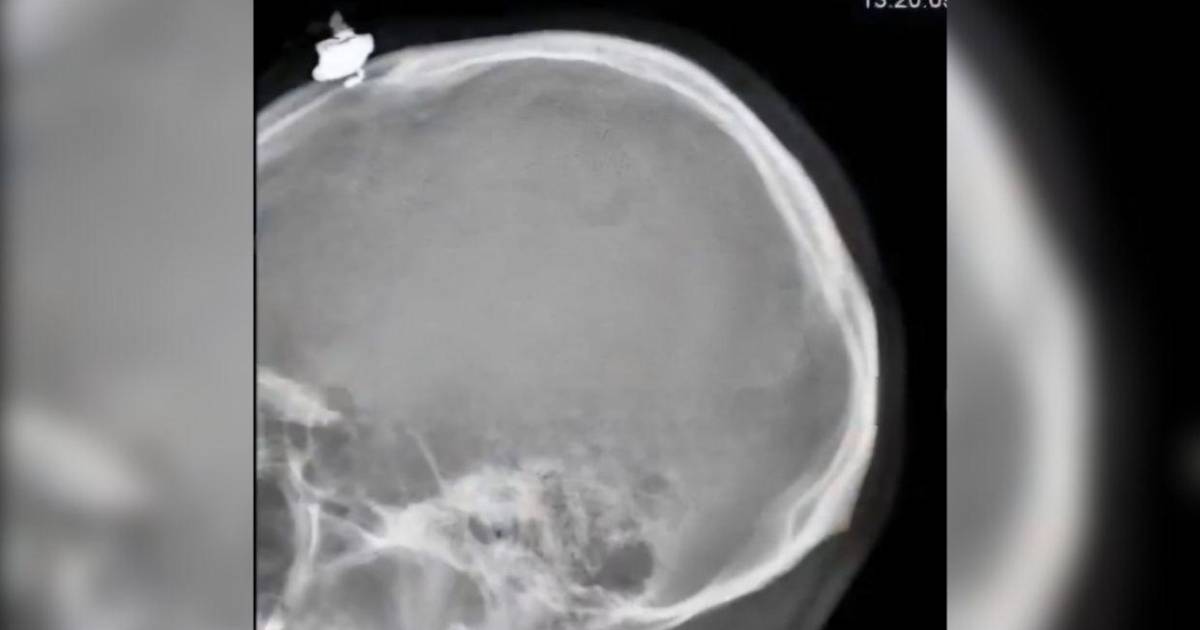

Luego de la agresión, el repartidor fue trasladado al Hospital del Sur, donde lo estabilizaron y atendieron su herida, aunque no le extrajeron la bala.

Nehemías Córdoba, portavoz del centro asistencial, explicó: “El ciudadano venía completamente bien, venía entablando conversaciones. Afortunadamente, no tocó el cerebro ni penetró ninguna de sus áreas. La bala solo tocó el hueso parietal de su cráneo”.